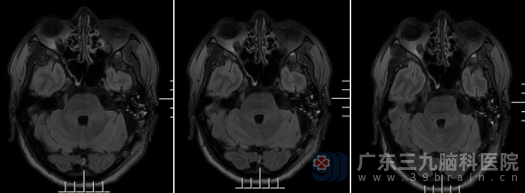

手术当天,神经外十科团队凭借精湛的技术和丰富的经验,前后历时6个小时,成功切除了囊肿(胆脂瘤)。术中,医生在显微镜放大下小心翼翼地避开周围重要的神经和血管,确保最大程度保护小脑、脑干及颅神经功能,雕刻式全切肿瘤。术后复查头颅MR显示:左侧桥小脑角占位病变已完全切除。病理报告进一步确认了诊断:符合表皮样囊肿。杨先生恢复顺利,神志清醒,对答切题,已能自主进食和活动,不久后便康复出院。